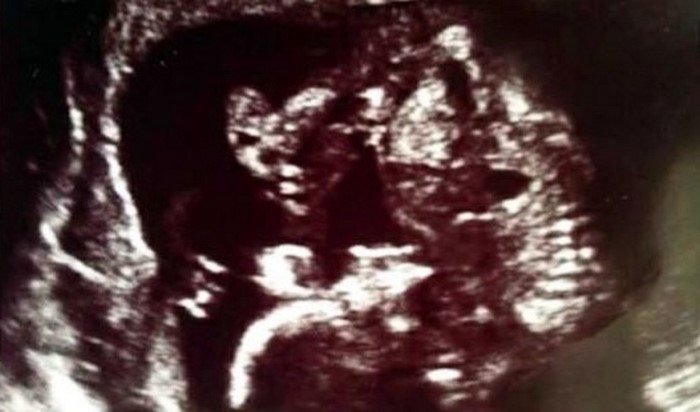

Неожиданности подстерегали троицу дальше. После одного из первых сеансов УЗИ врачи сообщили будущим родителям, что у них ожидается не один малыш, а двойня. Джоанна со Стивом мигом бросились покупать второй комплект вещей для новорожденных!

Однако Шанис начала подозревать, что парой близнецов дело не ограничится. Живот суррогатной матери, который еще недавно был совсем не большим, теперь рос как на дрожжах. В самом деле, новый сюрприз оказался настоящим потрясением для всех!

В конце концов на свет появилось не двое, а сразу трое крох — две девочки и мальчик. Сама беременность протекала практически без проблем, а Джоанна и Стив всегда предоставляли суррогатной матери помощь по первому ее слову.